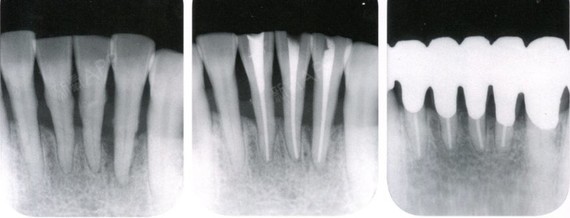

达到诊断质量的根尖片(x 光片取自笔者治疗过的病人)

虽然根尖片对口腔医生诊断牙病有很大帮助,但并不意味着一张根尖片就

一起来看片一根尖片的正常图像及应用